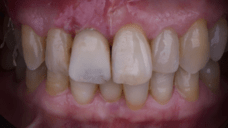

The main issue involved the upper right central incisor (tooth 1.1), which was devitalized and presented recurrent abscesses. Clinical and radiographic evaluation confirmed the presence of buccal bone wall resorption, leading to a significant defect in the alveolar ridge. This condition compromised both the hard tissue and the surrounding soft tissue, posing a challenge for achieving long-term stability and esthetic success in the anterior maxilla.

Due to the tooth’s location in the esthetic zone, the resorption and recurrent infections had a direct impact on the patient’s smile and overall confidence. She expressed dissatisfaction with the appearance of the affected tooth and emphasized the importance of restoring function and esthetics quickly. The clinical presentation highlighted the need for a treatment plan that combined immediate implant placement with simultaneous hard and soft tissue management to address the complex requirements of this case.